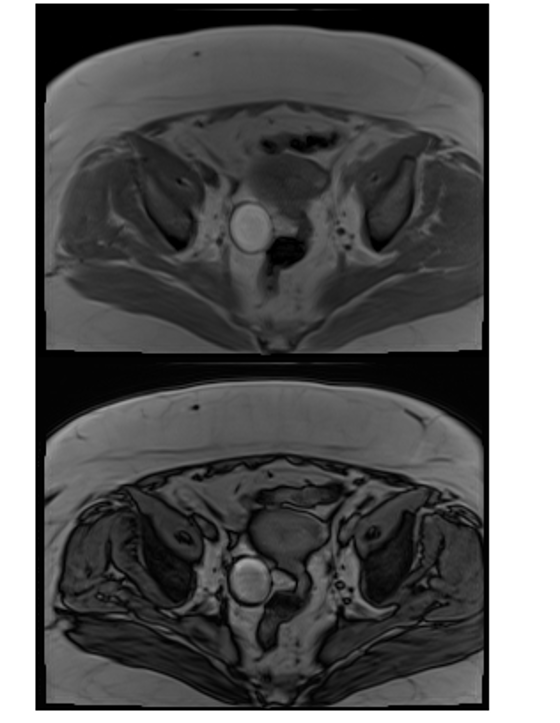

appearance of teratomas on in and out of phase imaging

ovarian teratomas are characteristically bright on IP and OOP imaging. Aka: they have MACROscopic fat and NOT microscopic fat. And because they don’t have microscopic fat, they won’t drop signal of OOP.